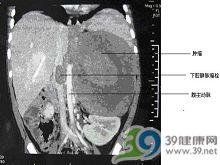

小兒下腔靜脈阻塞綜合徵

3.CT檢查 由腹部腫瘤所致阻塞採用CT檢查可明確阻塞的平面範圍另外對病變性質也能大致做出診斷CT結合對比劑的套用可清楚顯示不同平面的血管管腔精確診斷腔靜脈阻塞部位程度和可能的原因側支循環通路靜脈擴張度等 。

4.B超檢查 B超檢查在診斷下腔靜脈阻塞中起重要作用中山醫院19例肝段下腔靜脈阻塞的病人B超檢查結果與下腔靜脈造影基本相同1例下腔靜脈合併上腔靜脈阻塞X線造影顯示下腔靜脈在第9胸椎上緣水平處阻塞因上腔靜脈阻塞無法插入導管造影不能確定病變範圍但B超檢查發現在距心臟入口約20mm處下腔靜脈內有4mm厚的隔膜B超檢查準確方便甚至有時可彌補造影的不足並可篩選病人作下腔靜脈造影的主要檢查方法可見肝臟腫大腹水等